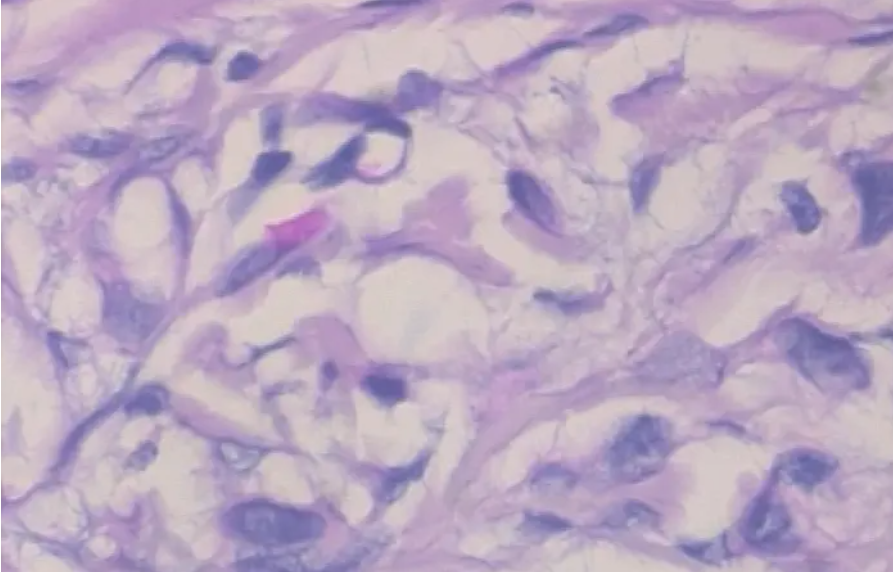

3.2 病变样本

然后我将数据集分成两组,分别具有80%和20%图像的训练集和测试集。让我们看一些样本良性和恶性图像